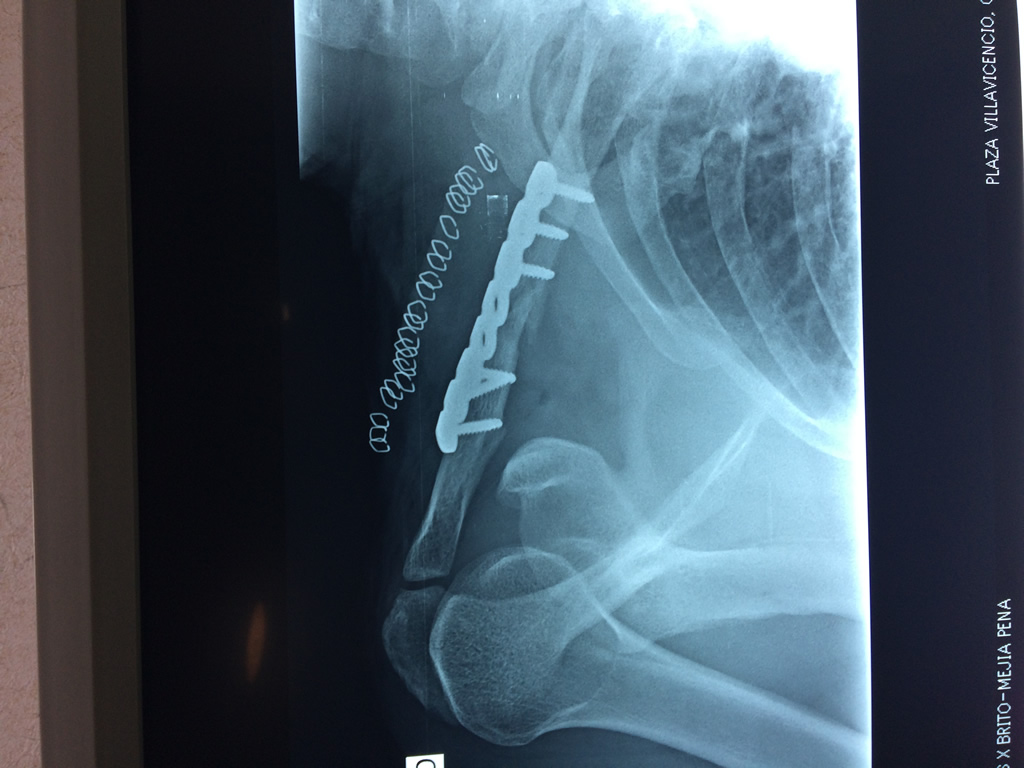

Clavícula

La clavícula es un hueso largo, con forma de "S" itálica, situado en la parte anterosuperior del tórax. Junto con la escápula forman la cintura escapular. Se puede palpar por toda su longitud y se extiende del esternón al acromion de la escápula, siguiendo una dirección oblicua lateral y posterior.

Se considera el único medio de unión entre el miembro superior y el tórax. A pesar de su aspecto, similar al de un hueso largo, posee una estructura semejante a la de un hueso plano, ya que carece de epífisis y de diáfisis, lo que la harían entrar dentro de la clasificación de hueso largo. Carece de un canal medular propiamente dicho.